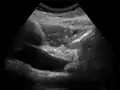

توسع القناة الصفراوية المشتركة بسبب ورم الأمبولي.